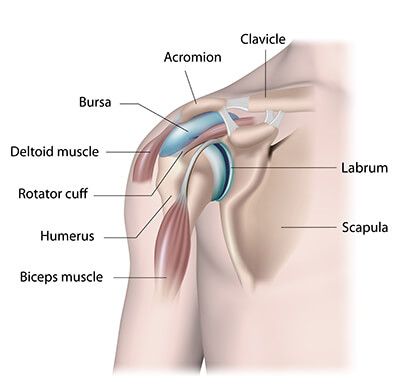

Shoulder Joint Preservation

The shoulder joint stands as one of the body's most intricate joints, linking the upper arm bone (humerus) to the shoulder blade (scapula). This remarkable joint offers an extensive range of motion in the arm, granting essential mobility. However, this impressive mobility comes at the cost of stability, making the shoulder joint susceptible to injuries and instability due to its complexity.